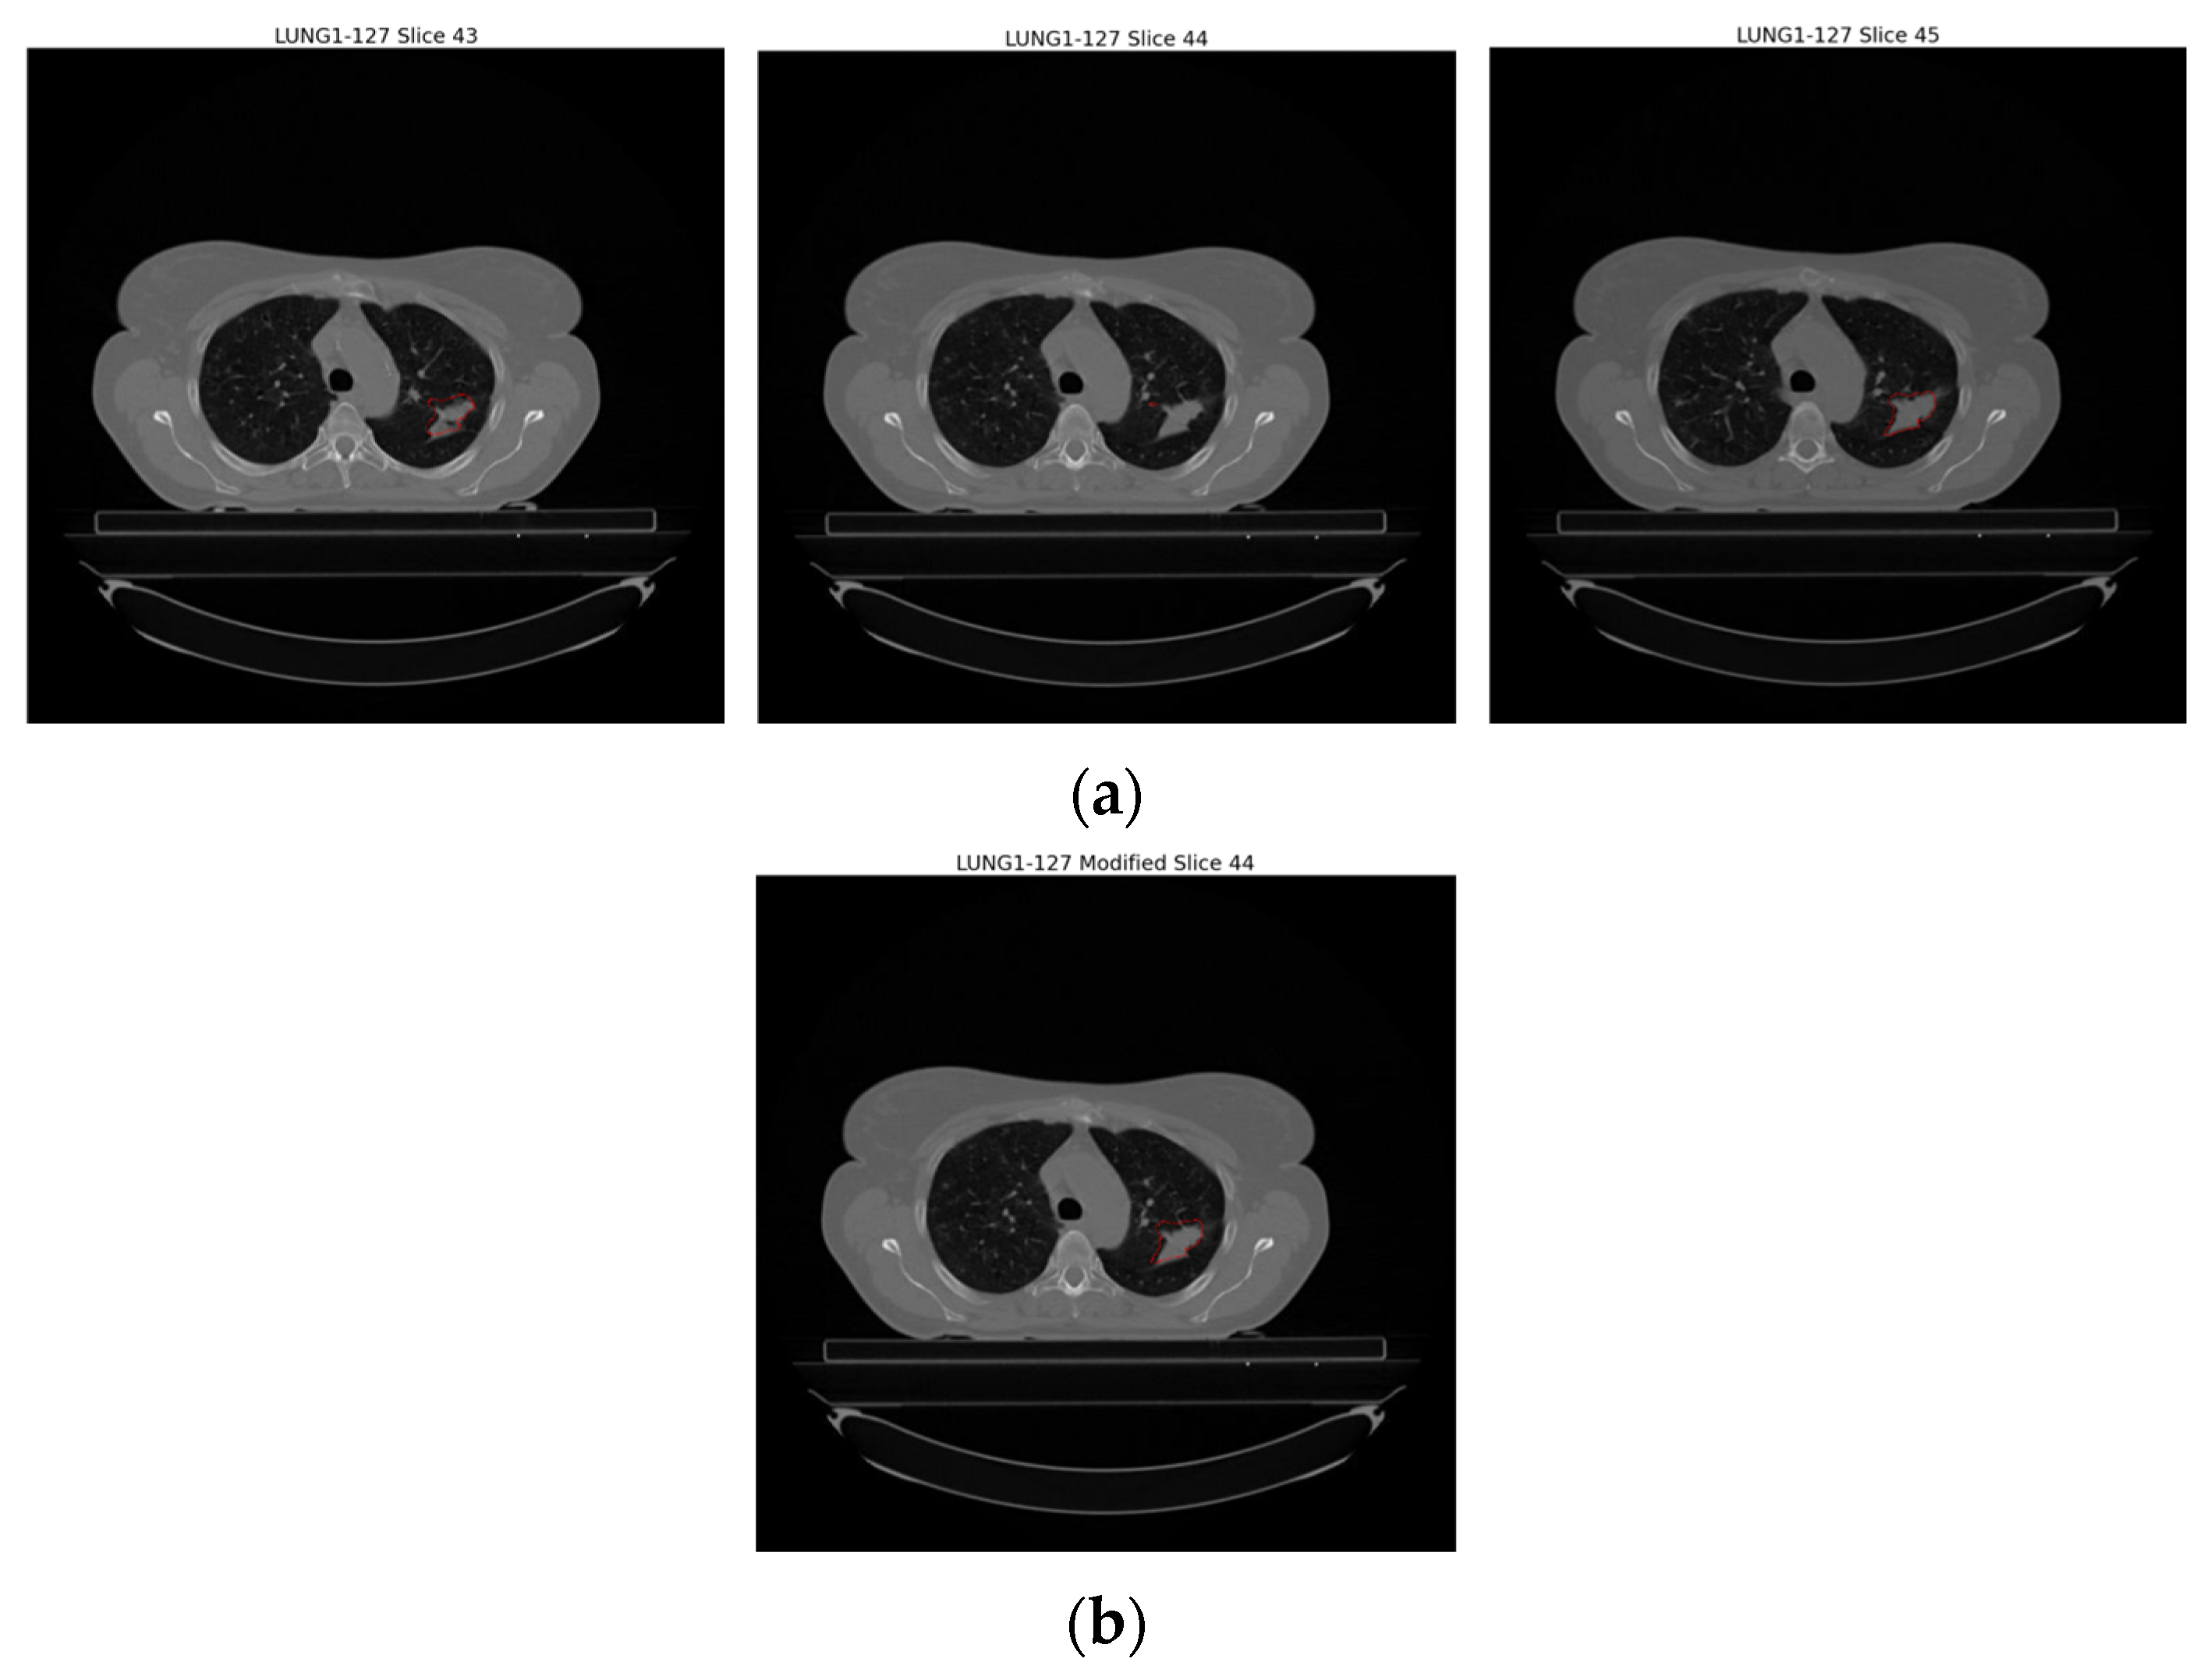

Upon examination of Figure 4, it is evident that GTV-1 information is absent in each slice. As a result of a detailed analysis of the Lung1 dataset, Braghetto stated that 5 patients were incorrectly segmented due to incorrect labeling of tumor regions, 62 patients due to interpolation of segmentation images in consecutive slices, and 3 patients due to the presence of more than one tumor in one image [23]. The representation of each error type is given in Figure 5.

Improper images in the dataset given in the previous section were re-examined and solutions were developed against these incorrectly segmented images. As a result of the analysis, no solution was developed in Figure 5a because it was not possible to verify the error type by the clinician. Against the error type in Figure 5b, when there were sudden changes in the number of pixels covering the regions with each GTV-1 label, the relevant error was detected and the GTV in the slice where the error was found was made by interpolating between the slice before and the slice after where the errors were found. Figure 6 shows the update in the slice where the error was found. Against the error type in Figure 5c, it was determined whether the tumor was on the right or left, and only one region was focused on.

Figure 6. Illustration of the incorrectly segmented slice caused by interpolation in sequential segmentation in slices of an example patient (LUNG1-127). (a) Original version of Slice 43, Slice 44, Slice 45, (b) interpolation of Slice 44 based on Slice 43 and Slice 45.